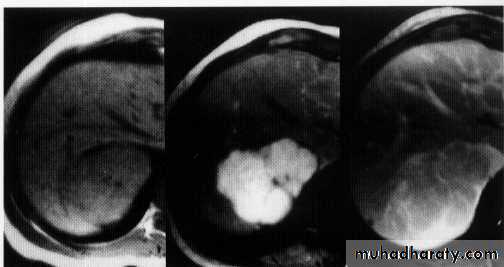

hemangeoma

Liver abscess

Hepatic , renal cyst